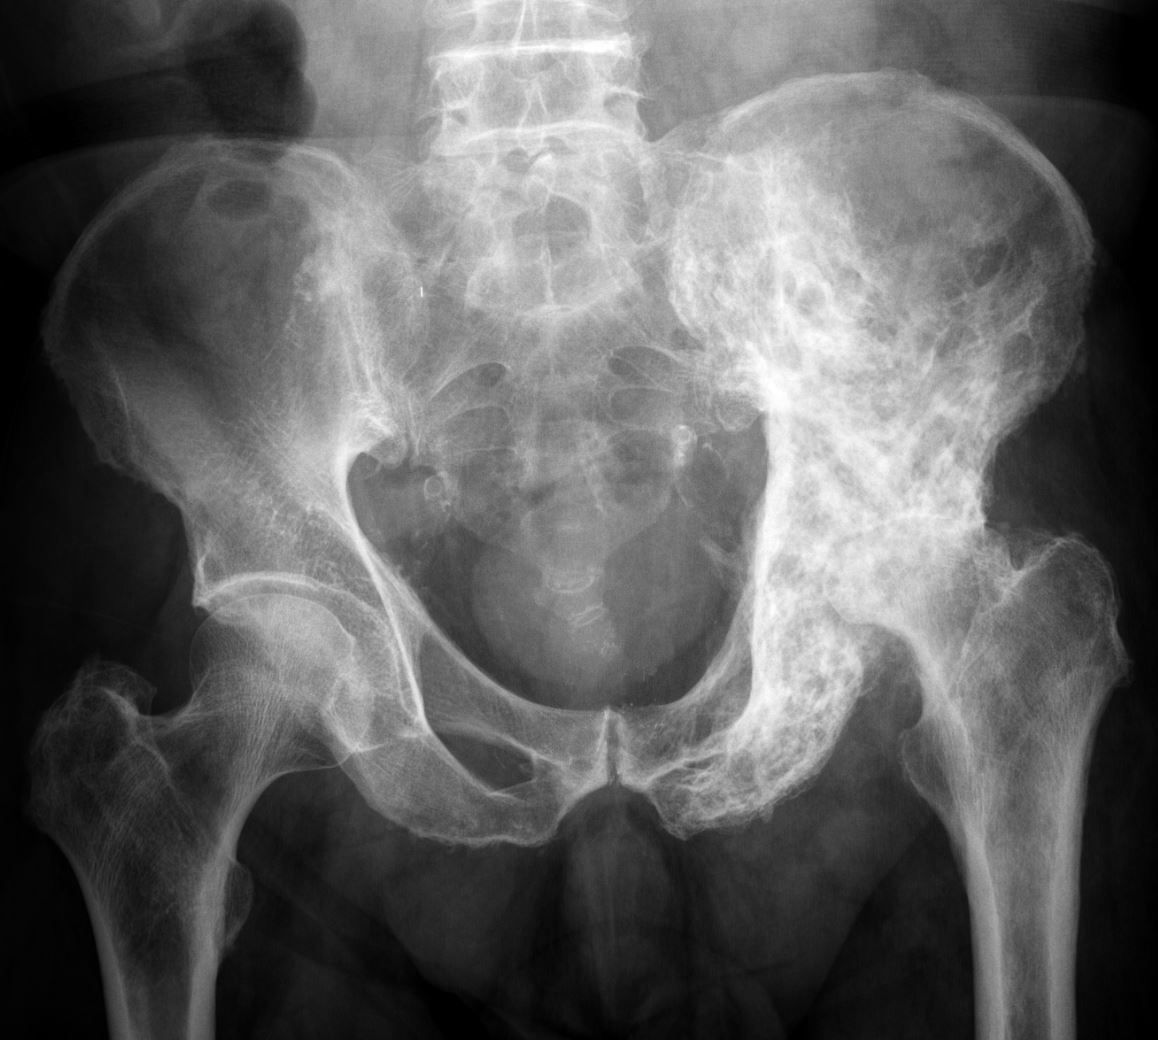

From radiopaedia.org

Paget disease pelvis Image Paget's Disease Left Hip Icd 10 They also might break easily. A chronic condition in which both the breakdown and regrowth of bone are increased. M88.88 is a billable diagnosis code used to specify osteitis deformans of other bones. Paget disease is a skeletal growth disorder in which abnormalities such as unusual bone growth can occur in. M88.1 is a billable diagnosis code used to specify. Paget's Disease Left Hip Icd 10.